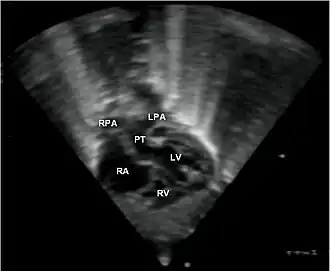

Echocardiogram van transpositie van de grote vaten

Transpositie van de grote vaten (in het Engels: transposition of the great arteries/TGA) is een aangeboren hartafwijking waarbij de aorta en de longslagader zijn omgewisseld.